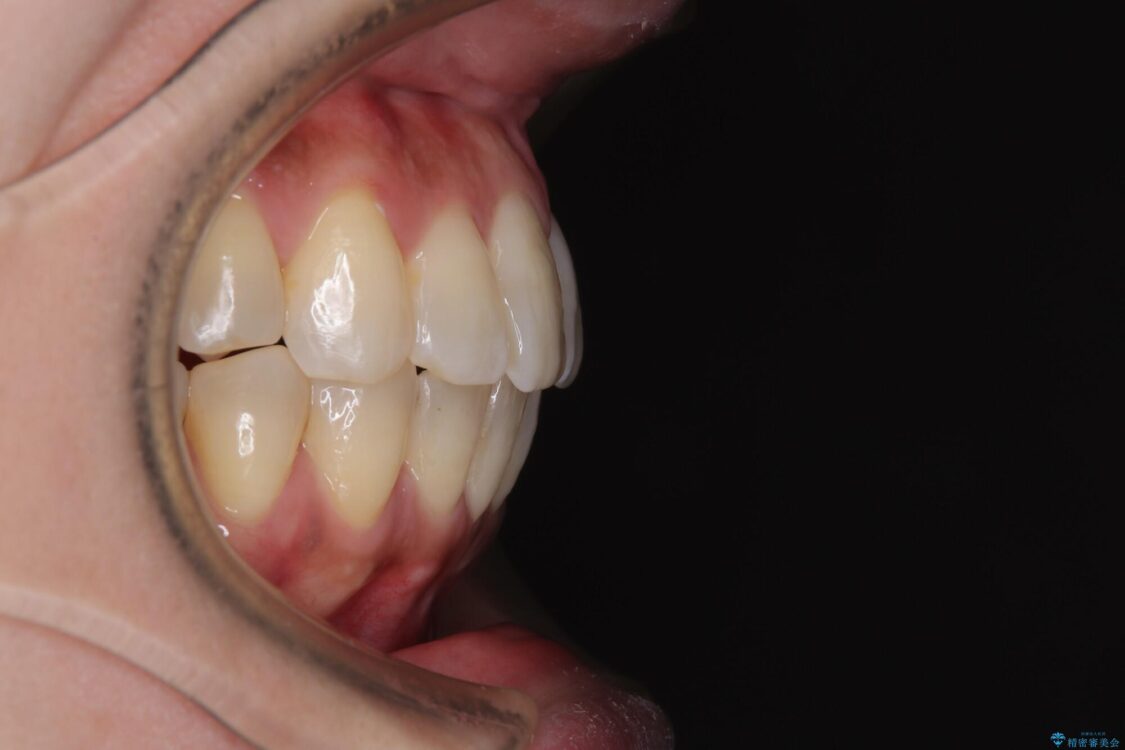

治療後について

歯の傾斜が改善され、インプラントによるクラウンが装着されたことで、物が挟まることもなくなりました。

治療後

• インビザラインによる矯正治療と奥歯のインプラント治療 治療後画像